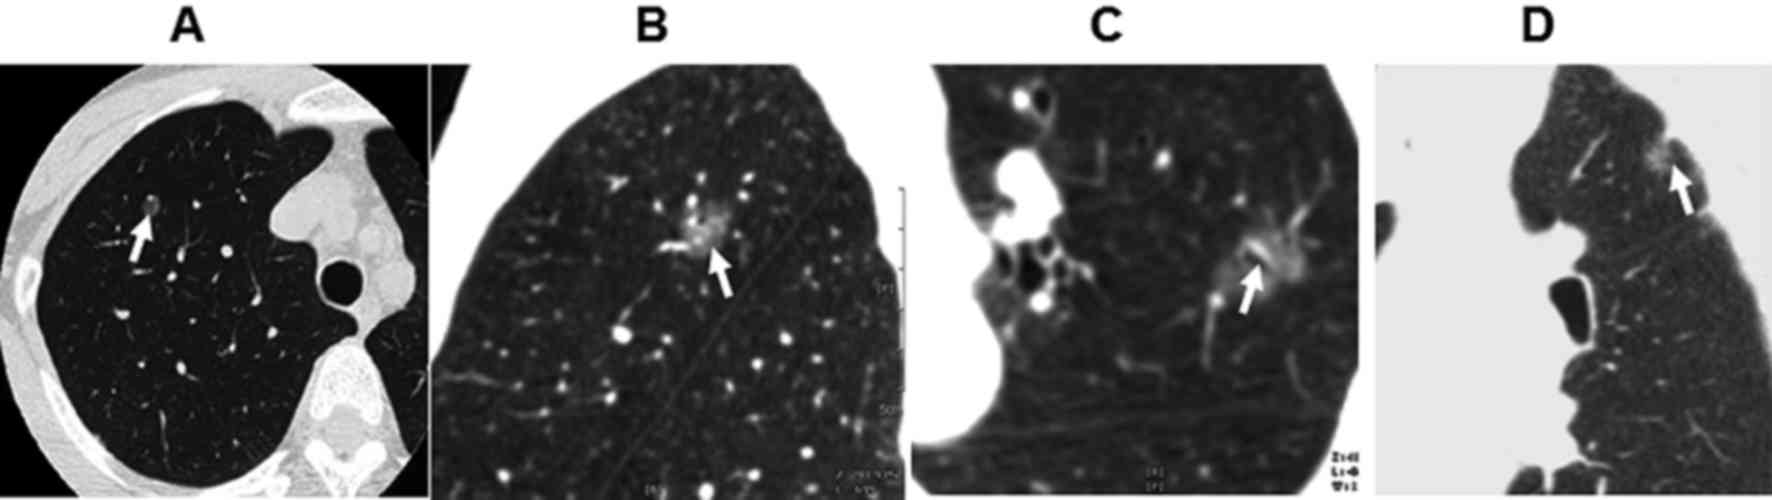

To determine the characteristics of lung lesions, HRCT scans were performed. As shown in Table I, among the 106 cases, there were 28 lesions in the right upper lobe, 21 lesions in the right middle lobe, 15 lesions in the right lower lobe, 19 lesions in the left upper lobe, 15 lesions in the left middle lobe and 8 lesions in the left lower lobe. Of the 106 cases, there were 12 lesions with diameter <1.0 cm, 36 lesions with diameter of 1.0–1.5 cm, 25 lesions with diameter of 1.6–2.0 cm, 19 lesions with diameter of 2.0–2.5 cm and 14 lesions with diameter of 2.5–3.0 cm. There were 20 lesions of round shape (Fig. 1A), 68 of oval shape and 18 lesions of irregular shape. There were 56 lesions with burring edge (Fig. 1B) and 32 lesions with leaf edge. There were 28 cases of air bronchogram (Fig. 1C) and 37 cases of pleural indentation surrounding the lesions (Fig. 1D). There were 16 patients with lesions of 20–55 HU in enhanced CT scan. There was no obvious necrosis or calcification in all cases.